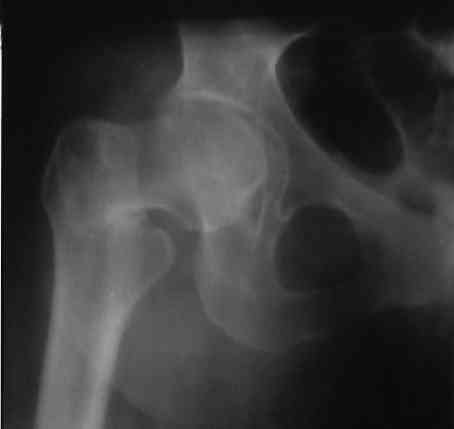

коллеги, отправляю снимок,раньше не получилось.

кто даст какой совет по остеосинтезу в свете остеопороза и рассеянного склероза?Я планирую синтез либо двухугловой пластиной,либо-130 градусной пластиной DHS,PFN просто нет И их приобретение не предвидится